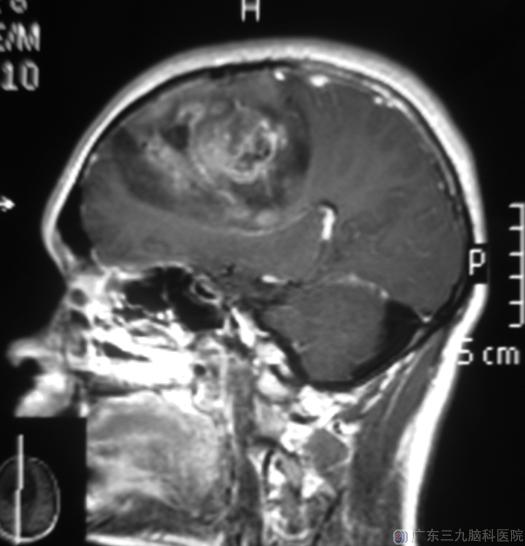

一个月前他出现头晕头痛,以头顶部为主,持续约1小时后可自行缓解;一周前双手出现不自主地抖动,每次持续约2分钟左右。当地医院头颅CT检查:右侧额叶占位。广东三九脑科医院头颅MR提示:右侧额叶示一巨大不规则形占位性病变,大小约79.0mm×73.2mm×69.4mm,中线结构向左偏,中脑受压变形。

由综合神经外科鲁明主任主刀,在术中唤醒麻醉下行右侧额叶巨大占位切除术。术前导航定位,显微镜下见红色肿瘤组织,与周围正常脑组织分界尚清;分离分块切除肿瘤组织,予超声吸引器将肿瘤全切。术后小陈的语言、肢体活动均正常。病理结果:少突星形细胞瘤伴多灶钙化(WHO II 级),局部区域呈间变型少突星形细胞瘤(WHO III级)。后期小陈还需接受进一步的放射治疗。